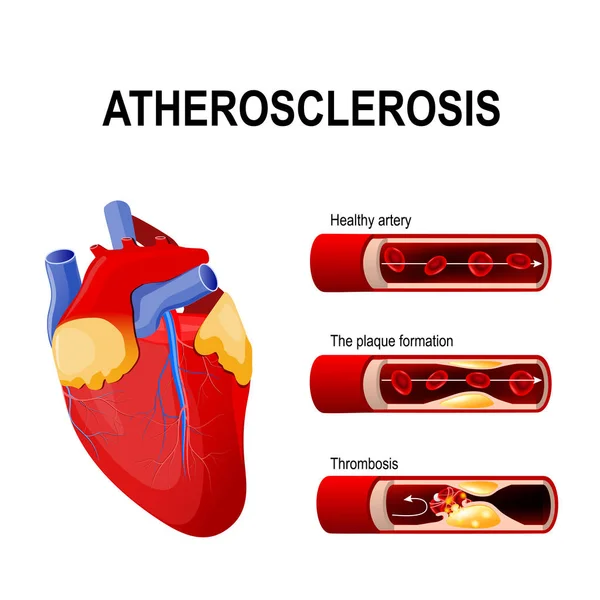

Atherosclerosis. Fibrous Plaque Formation Stock Vector – Image: 52546285

Atherosclerosis stock vector. Illustration of cardiovascular – 39305436

Normal Artery And Unhealthy Artery Stock Vector – Image: 52223409

Atherosclerosis Stages: Healthy Artery, Plaque Formation, and …

Arteriosclerosis / atherosclerosis – Symptoms and causes – Mayo Clinic